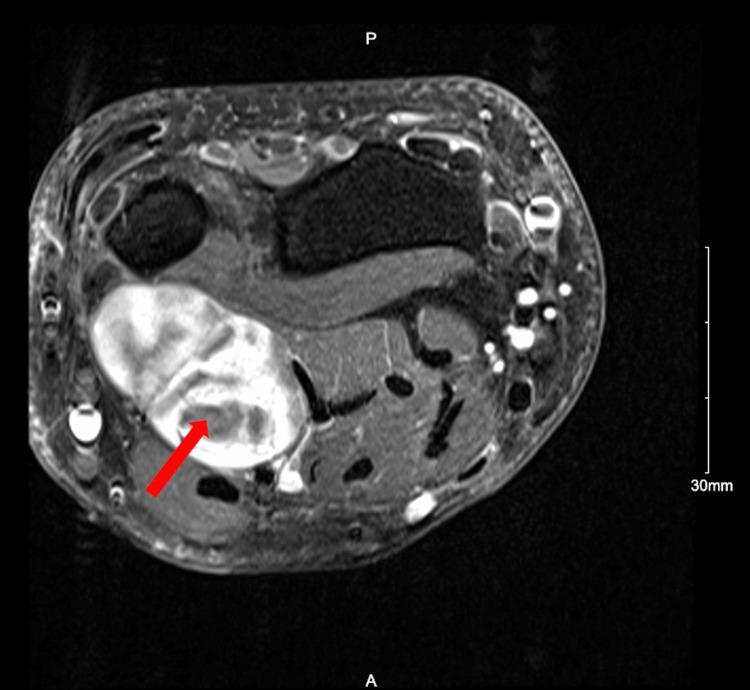

While peripheral nerve schwannomas have a relatively low incidence, schwannomatosis, the condition in which one forms multiple recurring schwannomas, is an even rarer phenomenon and can be hard to detect given its ability to mimic other conditions. We report a case of a 35-year-old male who presented with a mass in his left wrist and forearm, volar pain in his forearm, and numbness in his fingers. Magnetic resonance imaging (MRI) revealed a bilobed heterogeneous neural sheath tumor in the distal left ulnar nerve. The tumor was resected including extensive internal neurolysis using a Zeiss operative microscope. Post-operative biopsy confirmed an encapsulated schwannoma. The patient did well initially but developed worsening pain in his forearm and weakness. He had persistent paresthesias in the ulnar nerve distribution. He underwent a repeat MRI almost one year later, which showed thickening of the ulnar nerve proximal to the area of resection with an 8.5 mm hyperintense nodule. The patient underwent a subsequent resection with extensive neurolysis, which confirmed that the mass was a benign non-invasive schwannoma. At six weeks post-surgery, the patient's forearm pain was significantly improved and his range of motion returned to baseline. Our case demonstrates the importance of post-operative follow-up in schwannomas with appropriate imaging if symptoms persist or recur.

虽然周围神经鞘瘤的发病率相对较低,但神经鞘瘤病(即形成多个复发性神经鞘瘤的病症)是一种更为罕见的现象,并且鉴于其能够模仿其他病症,可能难以检测。我们报告一例35岁男性病例,该患者表现为左手腕和前臂有肿块、前臂掌侧疼痛以及手指麻木。磁共振成像(MRI)显示左尺神经远端有一个分叶状的异质性神经鞘瘤。使用蔡司手术显微镜切除肿瘤,包括广泛的内部神经松解术。术后活检证实为包膜性神经鞘瘤。患者最初情况良好,但前臂疼痛加重且出现无力。他在尺神经分布区域持续存在感觉异常。近一年后他接受了重复MRI检查,结果显示切除区域近端的尺神经增粗,有一个8.5毫米的高信号结节。患者随后接受了再次切除及广泛的神经松解术,证实该肿块为良性非侵袭性神经鞘瘤。术后六周时,患者的前臂疼痛明显改善,活动范围恢复到基线水平。我们的病例表明,对于神经鞘瘤,如果症状持续或复发,进行适当影像学检查的术后随访非常重要。